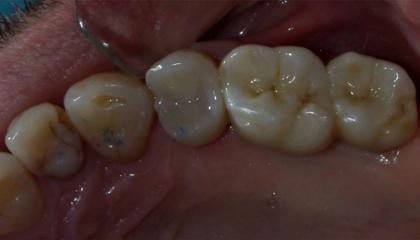

After

Zirconia Implants